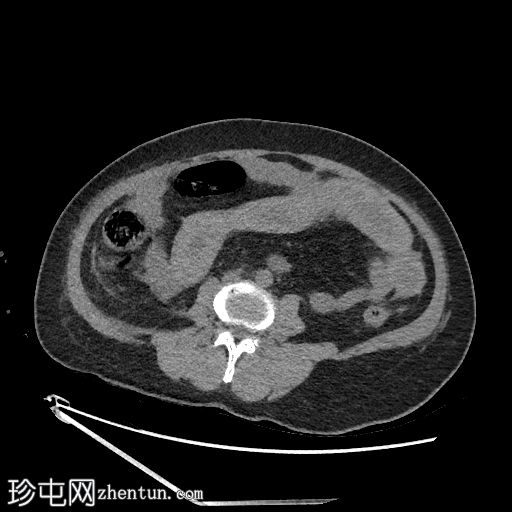

轴位

平扫

空肠(长段,60 cm)肠壁弥漫性节段性增厚。肠壁呈高密度影,平扫CT值约为56 HU,并可见强化。

可见肠系膜水肿和血管充血,以及少量腹水。

肠系膜上动脉和静脉通畅,未见血栓。

影像学表现最提示黏膜下出血。

鉴别诊断包括感染性肠炎。